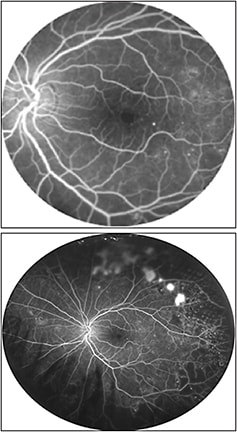

Figure 1. (Top) Traditional posterior-segment imaging of a patient with longstanding diabetes. Early background diabetic retinopathy changes are noted with no significant pathology requiring treatment. (Bottom) Optos UWF image of the same patient reveals significant pathology outside the traditional imaging. The peripheral retina shows areas of considerable ischemia and nonperfusion along with a large area of retinal neovascularization. This patient requires immediate intervention due to the extent of retinopathy noted on UWF imaging.